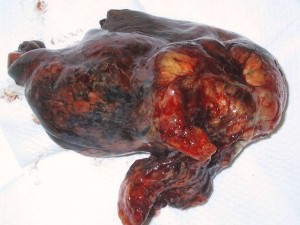

Гангрена(некроз)

Под гангреной (некрозом) понимают конечный результат распада тканей живого организма. Распад тканей возможен под влиянием как внешних, так и внутренних причин. Но всегда, вне зависимости от причины, гангрена развивается только в тех тканях, в которых имеются предпосылки для отмирания тканей, то есть так или иначе поврежденных. Учитывая, что для развития гангрены важно ухудшение трофики (питания) тканей, становится ясным, почему некроз развивается в основном отдаленных частях телах.